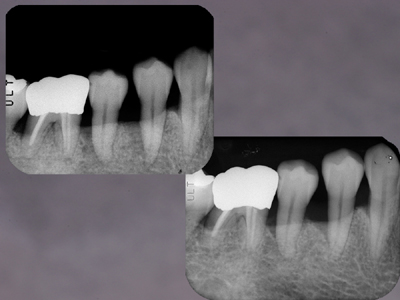

症例:’93初診時、右下45遠心に垂直性骨欠損がありプロービングデプス>8〜9mmでした。(当時の)新人DH Kによる非外科的ルートプレーニングにてPD2〜3mmに減少し、歯槽骨頂線が明瞭になりました。当時はそれを骨吸収の停止すなわち安定と考え一応のゴールの目安としていました。でも「その後」はみてはいませんでした。

かわかみ実験:レントゲンでの骨頂線の安定のイメージ

さいとう実験:扁心投影でこれほど違ってみえる